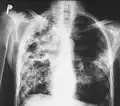

![]() Zdjęcie rentgenowskie klatki piersiowej osoby chorej na gruźlicę | |

Badanie RTG płuc

Objawy gruźlicy pierwotnej są często mało charakterystyczne, podobne do objawów grypowych. Bardziej zaawansowana postać gruźlicy daje zmiany w płucach w postaci nacieków gruźliczych, widocznych na zdjęciach radiologicznych.

Nacieki gruźlicze w prawym płucu oraz środkowym polu płuca lewego, rozpady (jamy) w górnym i środkowym polu płuca prawego, 2004

Bardzo zaawansowane zmiany. Zmiany gruźlicze przede wszystkim w polu górnym i środkowym oraz jama w szczycie prawego płuca, 2004

Zaawansowane zmiany swoiste (gruźlicze) w obu płucach, 2004

Zaawansowane zmiany swoiste w obu płucach, 2004

RTG klatki piersiowej u pacjenta z obustronną gruźlicą płuc